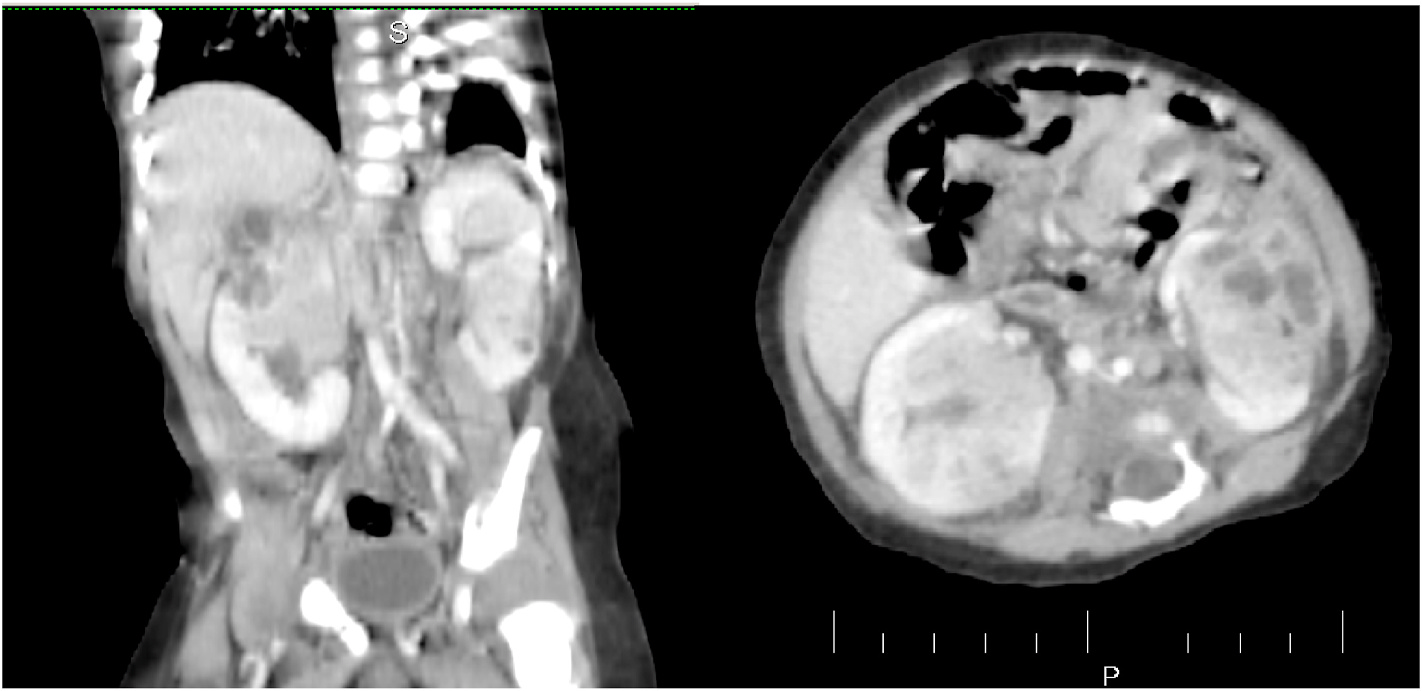

The initial blood analysis indicated significantly reduced phosphate levels 2.1 mg/dl. 25 (OH) D3 levels were notably low at 13 ng/ml, while FGF23 levels were markedly elevated at >35,000 RU/ml (normal range: 25-110 RU/ml). Osteocalcin and calcium fell within the appropriate range for the patient's age. Parathyroid hormone was elevated at 14 pmol/l (normal range: 1.6-6.9 pmol/l). Bone-specific alkaline phosphatase was significantly elevated at 754 mg/l. Renal function parameters, including creatinine, urea, and glomerular filtration rate, were within normal limits. Urine analysis indicated increased phosphate excretion. Radiographic examination showed a delicate, under-mineralized bone structure with a loss of definition at the calcification zone in the epiphyseal-metaphyseal interface and disorganization of the growth plate (Figure). Height measurements consistently fell below the third percentile (height: 78.3 cm, SDS -4.7), while bone age corresponded to that of a one-year-old (at the age of three). Abdominal ultrasound confirmed the presence of a left-sided multicystic dysplastic kidney, without any other intra-abdominal malformations.